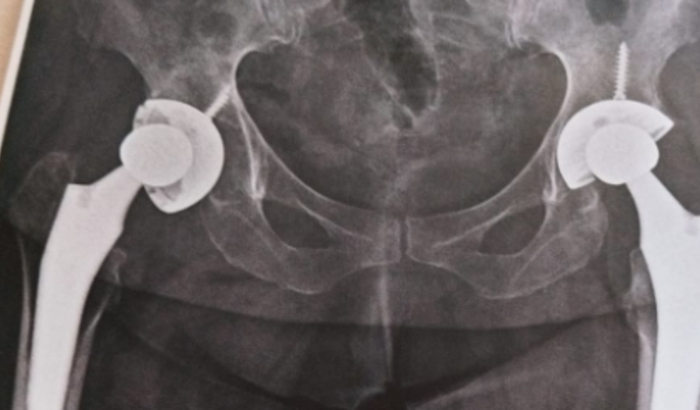

Olá a todos, me chamo Silvia dos santos sou moradora de Rio Branco do ivai e Hoje, venho compartilhar com vocês uma situação delicada que estou enfrentando e que requer a solidariedade, daqueles que se propôr em me ajudar. Há algum tempo, tenho lidado com uma prótese de quadril que se descolocou na minha perna direita e me deixou em condições dolorosa, debilitante e afetou significativamente a minha qualidade de vida, estou na espera pelo sus a mais de um ano, pra fazer a reparação mais, não estou mas aguentando tamanha dor, estou de cadeira de rodas e dependente de ajuda para tarefas básicas do meu dia a dia. Minha cirurgia está avaliada em 40 mil reais. Venho através desta mensagem pedir ajuda de todos familiares e amigos, qual quer valor simbólico será de grande ajuda. Desde já agradeço, primeiramente a Deus e minha família. Muito obrigada…O meu mandamento é este: Amem-se uns aos outros como eu os amei. João 15:12